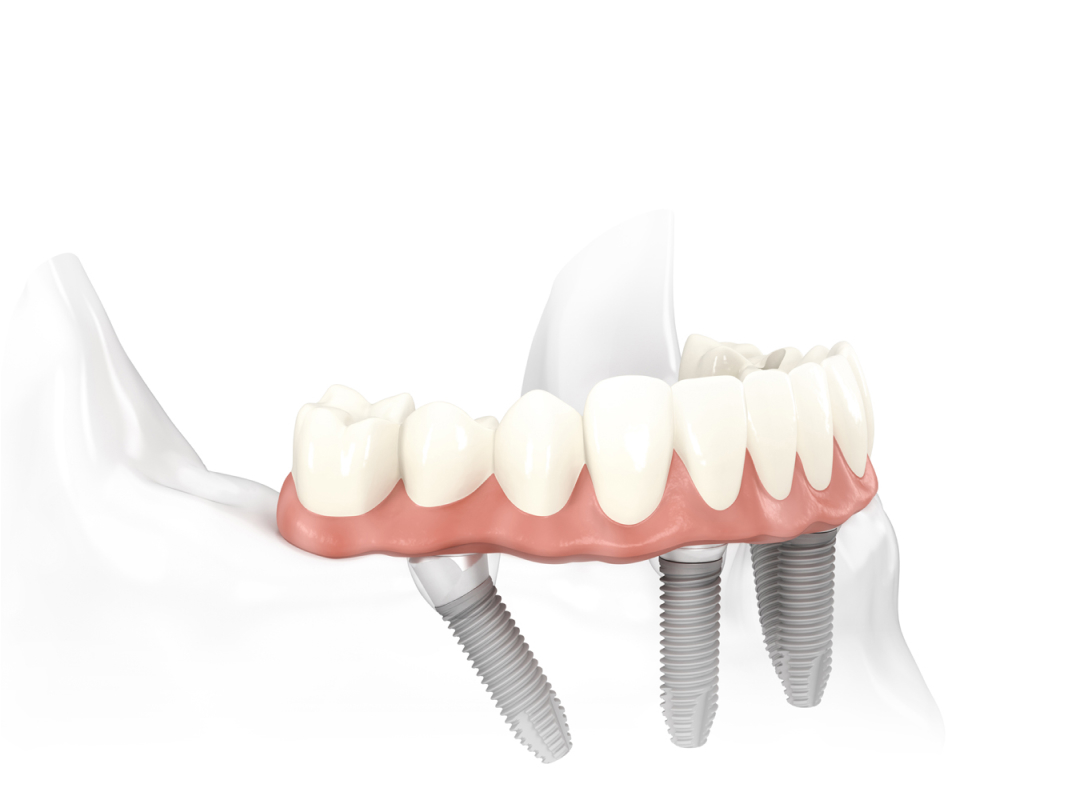

If you are a good candidate for ‘same day teeth on implants’, and would like to proceed with designing your new smile, the next step involves digital imaging. The digital scanning allows for digital design of your new smile and digital simulation of your dental implant surgery. Your current smile will be captured using facial scanning technology and your new smile will be perfected with specialised software.

While the ideal position and size of your teeth are designed on specialised ‘bite and smile design’ software, your surgery can be planned on specialised surgical planning software. A CT scan is obtained and loaded into the planning software to allow Dr. Currie to plan the appropriate number and size of dental implants for your surgery.

On the day of your surgery you will arrive in the morning and be given appropriate medications including some sedative medication to make you sleepy. Dr. Currie and his team then put all of the careful planning to work. The bad teeth are removed, dental implants are placed and a new set of teeth is fabricated to be attached to the implants.